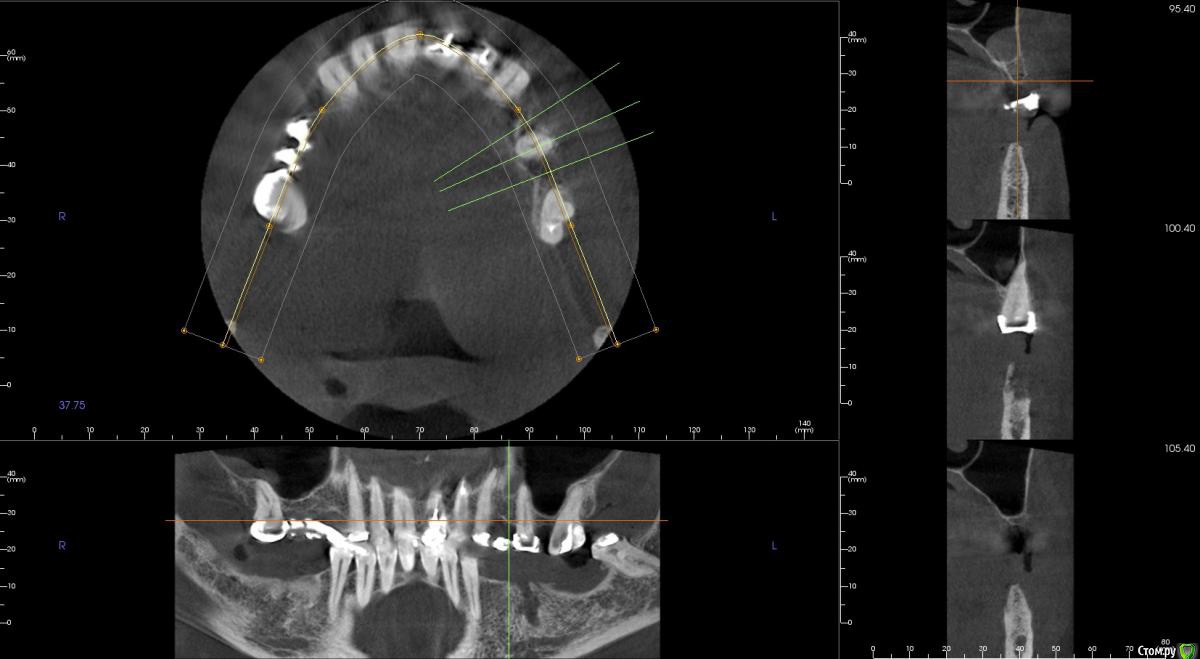

4ebstom Опубликовано 8 февраля, 2017 Поделиться Опубликовано 8 февраля, 2017 Спасибо за публикацию.Какова ширина гребня? Ссылка на комментарий

kamranchick Опубликовано 8 февраля, 2017 Автор Поделиться Опубликовано 8 февраля, 2017 Спасибо за публикацию.Какова ширина гребня?5мм сверху в области кристального модуля имплантата дальше около 7мм) Ссылка на комментарий